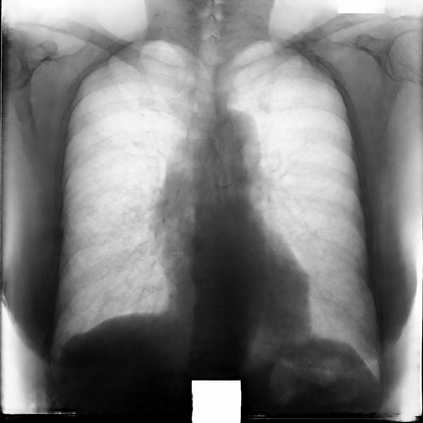

Multi-organ segmentation of X-ray images is of fundamental importance for computer aided diagnosis systems. However, the most advanced semantic segmentation methods rely on deep learning and require a huge amount of labeled images, which are rarely available due to both the high cost of human resources and the time required for labeling. In this paper, we present a novel multi-stage generation algorithm based on Generative Adversarial Networks (GANs) that can produce synthetic images along with their semantic labels and can be used for data augmentation. The main feature of the method is that, unlike other approaches, generation occurs in several stages, which simplifies the procedure and allows it to be used on very small datasets. The method has been evaluated on the segmentation of chest radiographic images, showing promising results. The multistage approach achieves state-of-the-art and, when very few images are used to train the GANs, outperforms the corresponding single-stage approach.